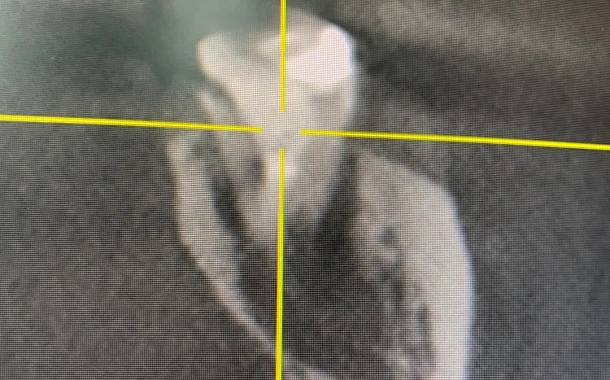

По 3D компьютерной томографии определяет возможность установки имплантата, немедленной фиксации временной коронки в день операции и объем пластических манипуляций. Совместно с врачом-стоматологом ортопедом планирует вид ортопедической конструкции и положение имплантата.

Компьютерная томография в формате 3D - важный диагностический инструмент стоматолога. На полученном объемном снимке стоматолог видит все нюансы вашей зубочелюстной системы: состояние костной ткани челюстей, зубов и височно-нижнечелюстного сустава. Именно томография позволяет доктору составить план и объем предстоящего оперативного вмешательства.